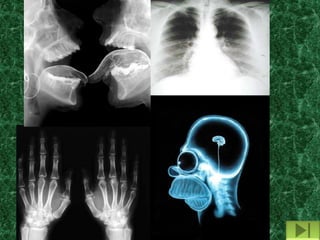

Raio X

Raios X

Os raios X foram descobertos em 8

de novembro de 1895, pelo físico alemão

Wilhelm Conrad Roentgen.

Raios X é a denominação dada à

radiação eletromagnética de alta energia

que tem origem na eletrosfera ou no

freamento de partículas carregadas no

campo eletromagnético do núcleo atômico

ou dos elétrons.

Raios X podem ser produzidos

quando elétrons são acelerados em

direção a um alvo metálico.